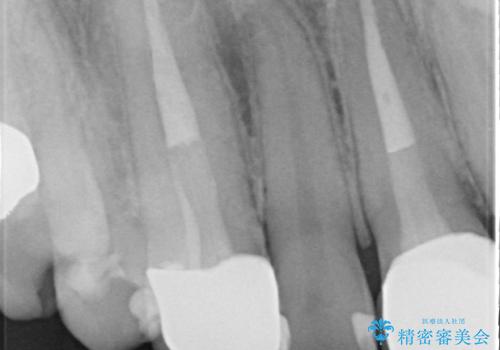

- 数年前に右上3の根管治療を行ったが、段々と色が気になってきたので、セラミックによる治療を行いたいといらっしゃった方の症例です。

再根管治療終了後、オールセラミッククラウンによる補綴を行いました。

- オールセラミッククラウン(sp)…¥130,000、仮歯…¥10,000、ファイバーコア…¥20,000費用は治療当時の料金となります